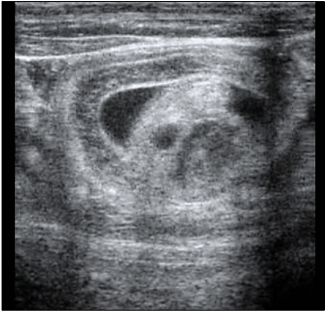

Um potro de sete meses, apresentando sinais de desconforto e distensão abdominal progressiva, foi encaminhado ao hospital veterinário. À avaliação ultrassonográfica registrou-se a imagem apresentada a seguir:

Enunciado 4509953-1

Com base nos achados, qual seria a etiologia mais provável do desconforto abdominal e a indicação terapêutica mais indicada para o caso?